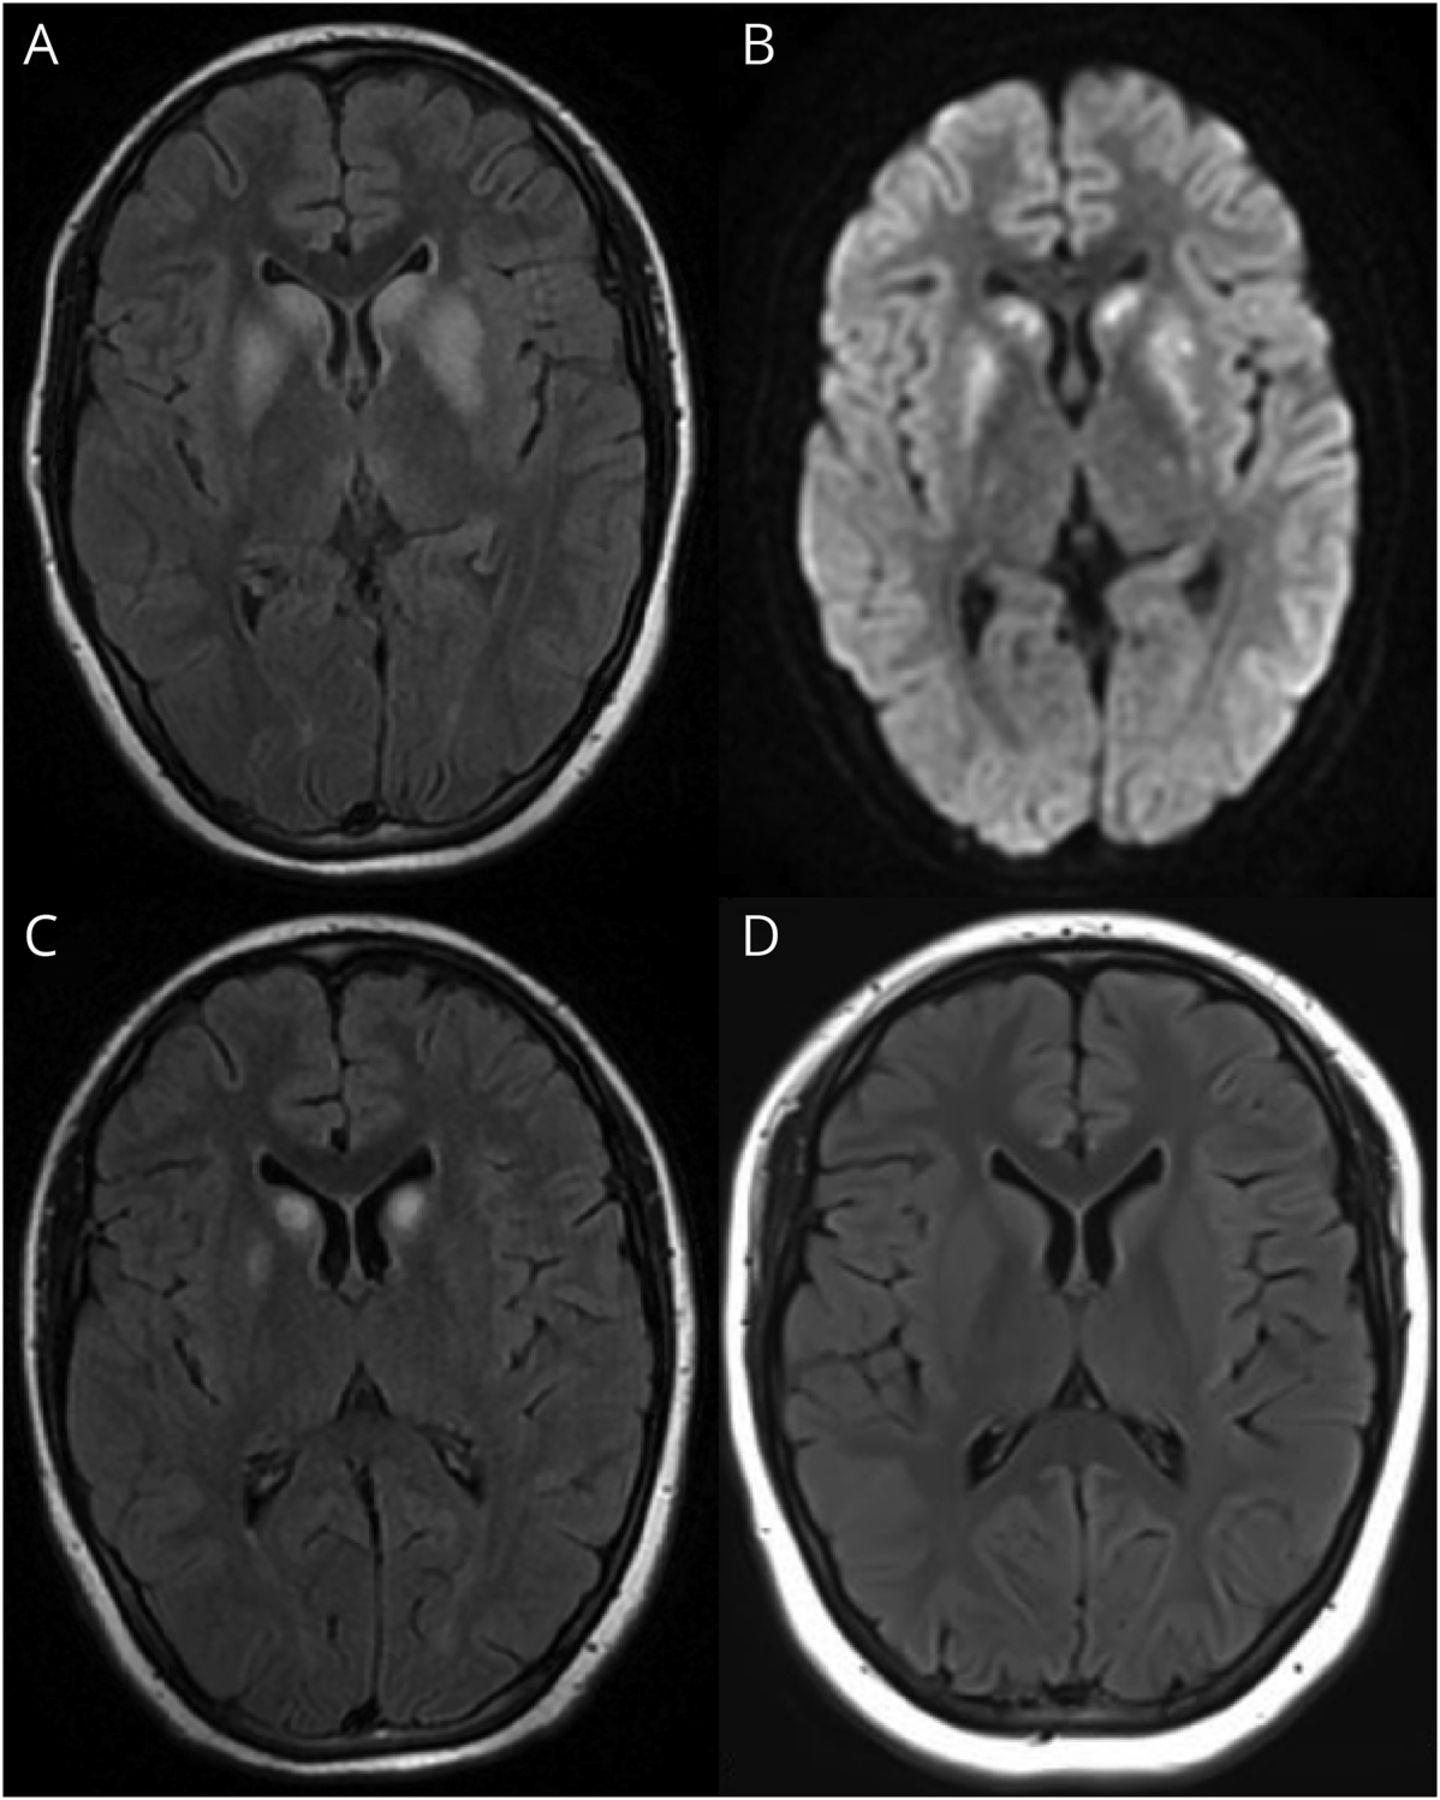

住院期间,我们观察到轻微受损的短期记忆力和稍微延长反应时间在病人相比,指出在入学。随后的认知评估揭示了注意力,轻度损伤计算,和记忆领域,评价语言和执行功能域还没有因为构音障碍和肢体的弱点。认知障碍提出脑功能障碍;因此,脑MRI表现。对称双边基底神经节的损伤被发现与hyperintensity T2 fluid-attenuated反转恢复,diffusion-weighted成像(驾车)hyperintensity,相应的表观扩散系数hypointensity,没有对比增强(图1中,A和B)。

(A, B)的大脑图像T2-FLAIR和驾车在发病。大脑图像T2-FLAIR (C)后1个月和1年(D)核黄素治疗。醉酒驾车= diffusion-weighted成像;天赋= fluid-attenuated反转恢复。

正常心脏超声排除心肌参与。核黄素(20毫克/公斤/天)推荐的治疗。8经过一个月,她的肌肉力量回到大约3/5,她能够独立行走。MRI复审显示较小的病变,符合改进的内存(图1 c)。1年的随访之后,她的症状,包括肢体麻木和弱点,认知功能受损和颅内病变,几乎完全解决(图1 d),而运动耐力恶化超过preonset指出。